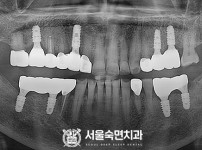

임플란트-전후사진4

치과를-선택할-때-꼭-확인하세요-서울숙면치과-임플란트-전후사진